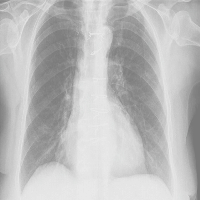

| Abstract | Ten years of lung function and radiological findings in six non-smoking asbestos exposed subjects who had increased mid-expiratory flow rate (FEF 25-75%) as the only functional abnormality were prospectively analysed. A biphasic change in FEF25-75% was noted. It initially increased up to the fifth year, and then a decrease was seen. In the final three years of the study, FEF25-75% reduction correlated well with a decrease in pulmonary capacity for CO (DLCO). During that time high resolution computed tomography (HRCT) probability scores correlated inversely with FEF25-75% and with DLCO, whereas chest radiography was unchanged (International Labour Organisation (ILO) profusion below 1/1). For five of the six subjects HRCT probability of asbestosis was intermediate. An increase in FEF25-75% in some asbestos exposed non-smoking workers may be one of the earliest functional signs indicative of future development of parenchymal asbestosis. Early asbestos related parenchymal abnormalities are seen more frequently on HRCT than on chest radiography. |